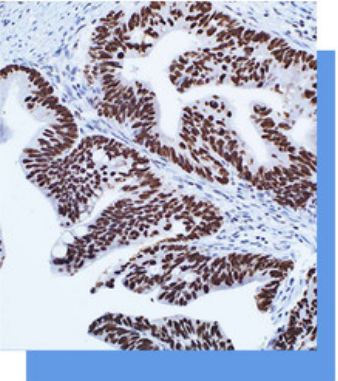

SATB2抗体试剂

SATB2是一种核基质相关的转录因子,作为染

色质重塑酶的分子对接点,利用辅助激活因子和辅

助抑制因子来控制核基因的表达。STAB2还调节

骨骼发育、成骨细胞的分化、调节免疫球蛋白的表

达。在正常组织中, 包括阑尾、结肠和直肠在内

的下肠粘膜基本上所有腺细胞中都可观察到STAB2

的强烈表达。STAB2也在神经内分泌细胞中表达。

在肿瘤组织中,STAB2可在结直肠癌起源的癌细胞

(包括神经内分泌肿瘤)中检测到。STAB2对结直肠

癌的敏感性为85%,联合CK20染色可进-步提高

到93%,